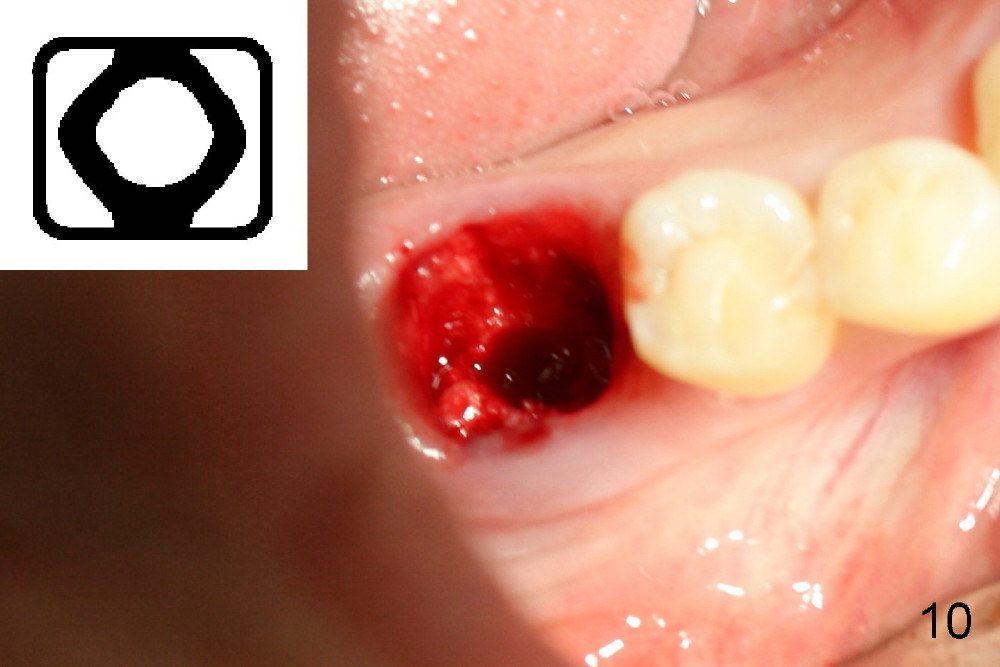

Septal bone is apparently pushed into the mesial and distal sockets (Fig.7 inset arrows) when a small round osteotomes is removed. The deeper portion of osteotomy is created by drills (Fig.8,9). The septal bone is further pushed mesiodistally as the osteotomy enlarges with combination of drills and osteotomes (Fig.10). A 6x17 mm tapered implant is placed with insertion torque >60 Ncm (Fig.11: I).